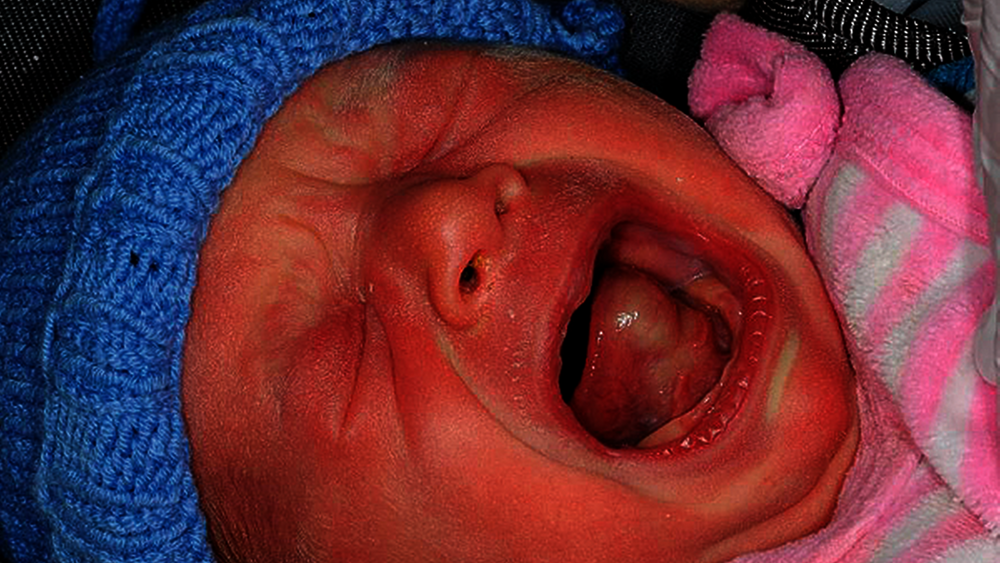

Im Anschluss an die Geburt zeigte sich bei einer kleinen Patientin eine Raumforderung im Bereich des vorderen Zungendrittels von circa 1 cm Durchmesser (Abbildung 1), so dass sie von der Geburtshilfe konsiliarisch in der Mund-, Kiefer-, Gesichtschirurgie vorgestellt wurde. Die Raumforderung war im Tastbefund kugelig, prallelastisch und gut abgrenzbar. Die Patientin war im Allgemeinzustand stabil, Probleme bei der Nahrungsaufnahme oder der Atmung bestanden nicht. In einer Sonografie zeigte sich keine relevante Kompression oder Verlegung umliegender Strukturen.